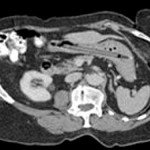

- Huszonöt év után működő filctollat találtak az orvosok egy brit nyugdíjas gyomrában bejegyzéshez a hozzászólások lehetősége kikapcsolva

Huszonöt év után egy teljesen jó állapotban lévő és működőképes filctollat távolítottak el az orvosok egy brit nyugdíjas ...